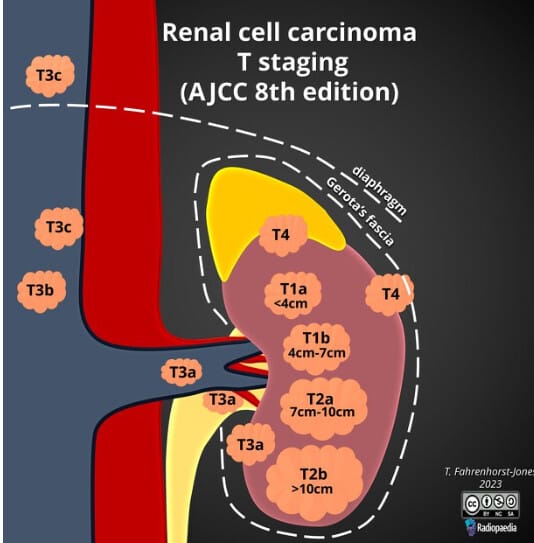

Renal cell carcinoma 병기

신세포암(Renal cell carcinoma, RCC)의 병기는 종양의 크기와 신장을 넘는 침범 정도, 림프절 전이 여부, 원격 전이 여부에 따라 TNM Staging 체계로 분류합니다. 병기는 예후 예측과 치료 결정에 매우 중요합니다.

Fahrenhorst-Jones T, Renal cell carcinoma T staging (AJCC 8th edition). Case study, Radiopaedia.org (Accessed on 07 May 2025) https://doi.org/10.53347/rID-177572

| Stage III (T3 또는 N1, M0) |

| 종양이 신장을 넘어 신정맥, 대정맥 또는 주변 지방조직에 침범하거나 림프절 전이가 있으나 원격 전이는 없음. |

| Stage IV (T4 또는 M1) |

| 종양이 인접 장기(부신, 대장 등)를 침범하거나, 원격 전이(폐, 뼈, 간 등)가 있는 경우. |

Stage I~II는 국소 질환으로 간주되어 수술적 절제를 우선 시행함, Stage III는 국소 진행, Stage IV는 전이성 질환으로 면역치료와 표적치료가 중요합니다.